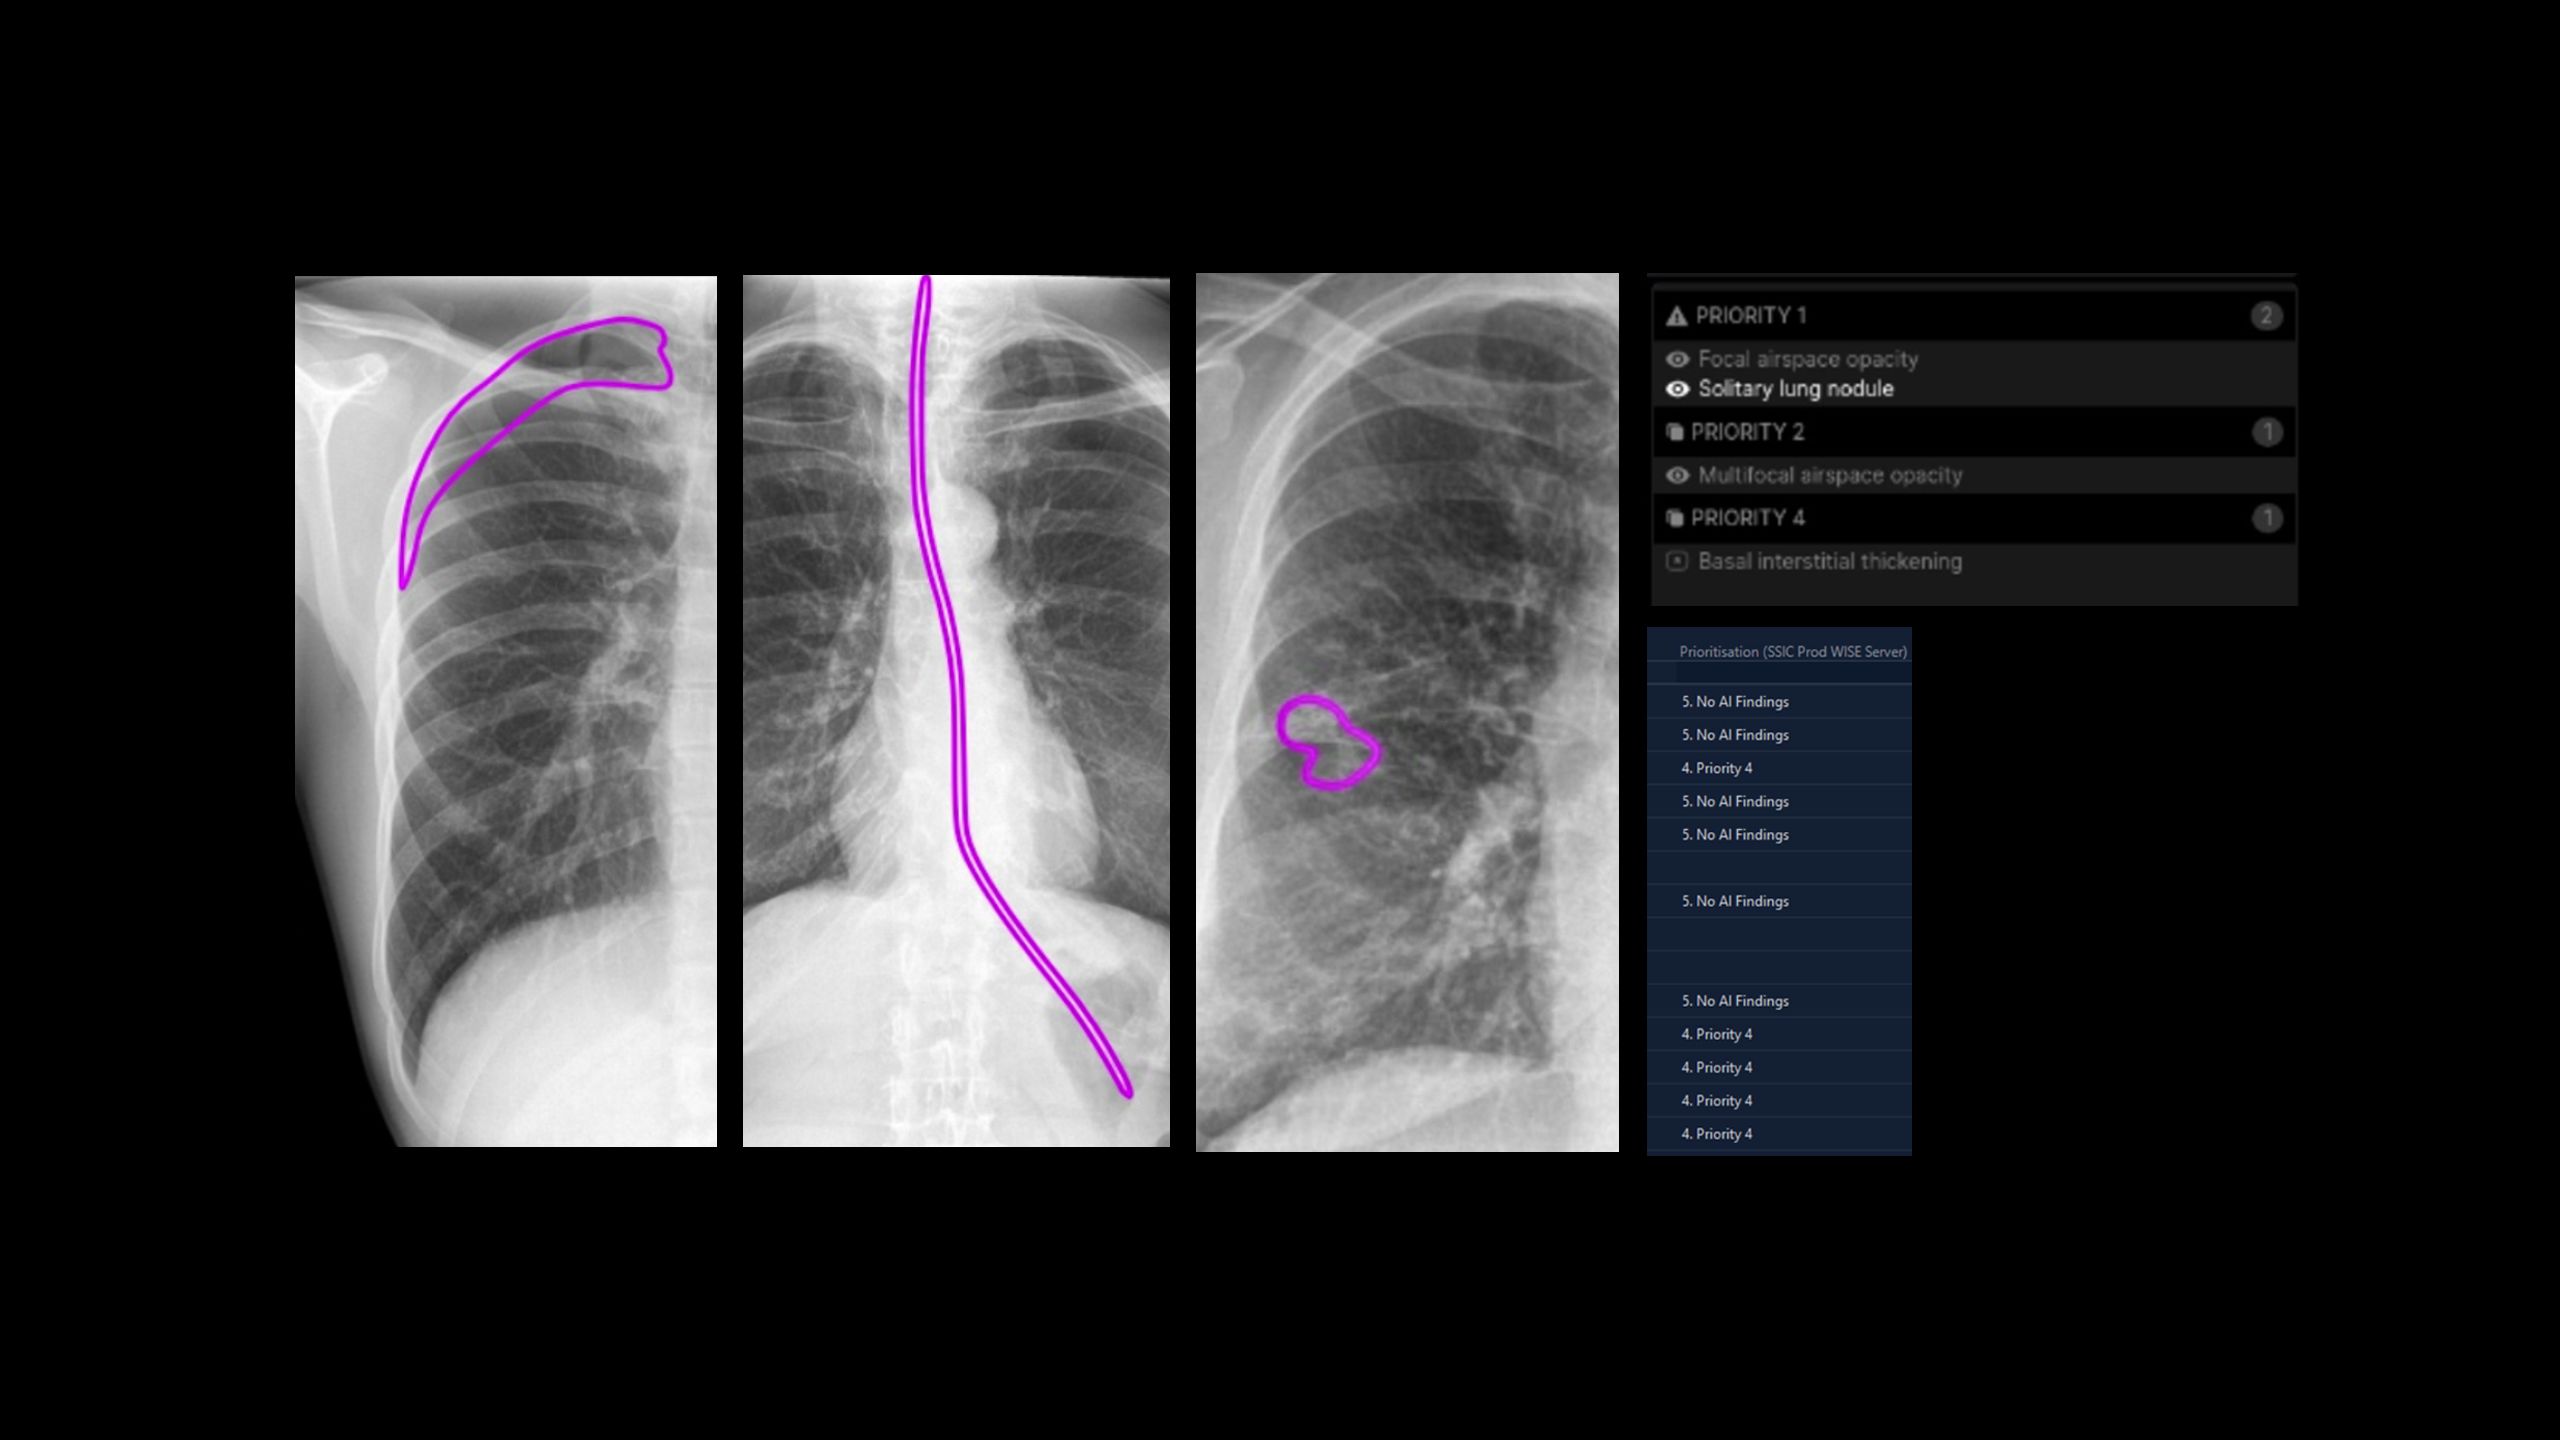

During Synergy’s visit, Mary demonstrated the usage of the program on a dummy scan. She explains that the technology doesn’t pinpoint any one pathology – it checks for everything. The system also shows confidence levels for its diagnoses marked on the scan itself.

The Harrison.ai chest X-ray tool uses AI to examine chest X-rays and identify up to 124 possible health issues in patients’ lungs, including serious conditions such as cancer and collapsed lungs.